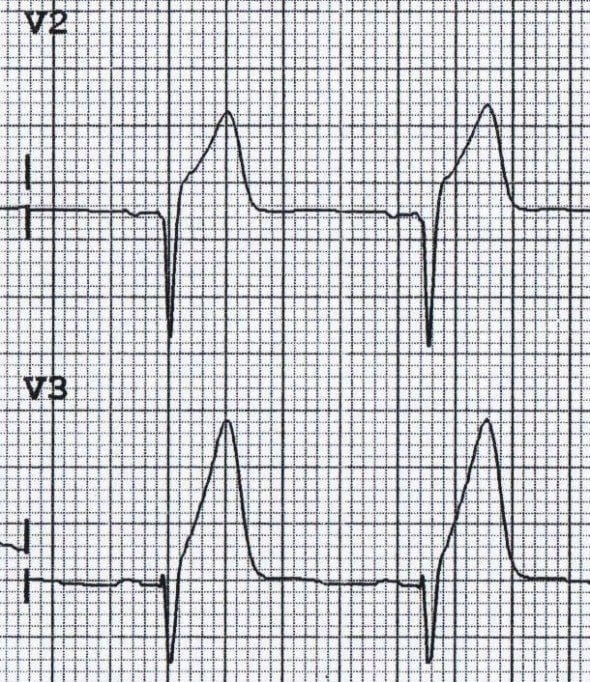

ECG Example – Hyperacute T wave

This ECG demonstrates hyperacute T waves, secondary to an anterior STEMI, concurrent ST elevation is also visible.

© Life in the Fast Lane. Licensed under CC BY-NC 4.0